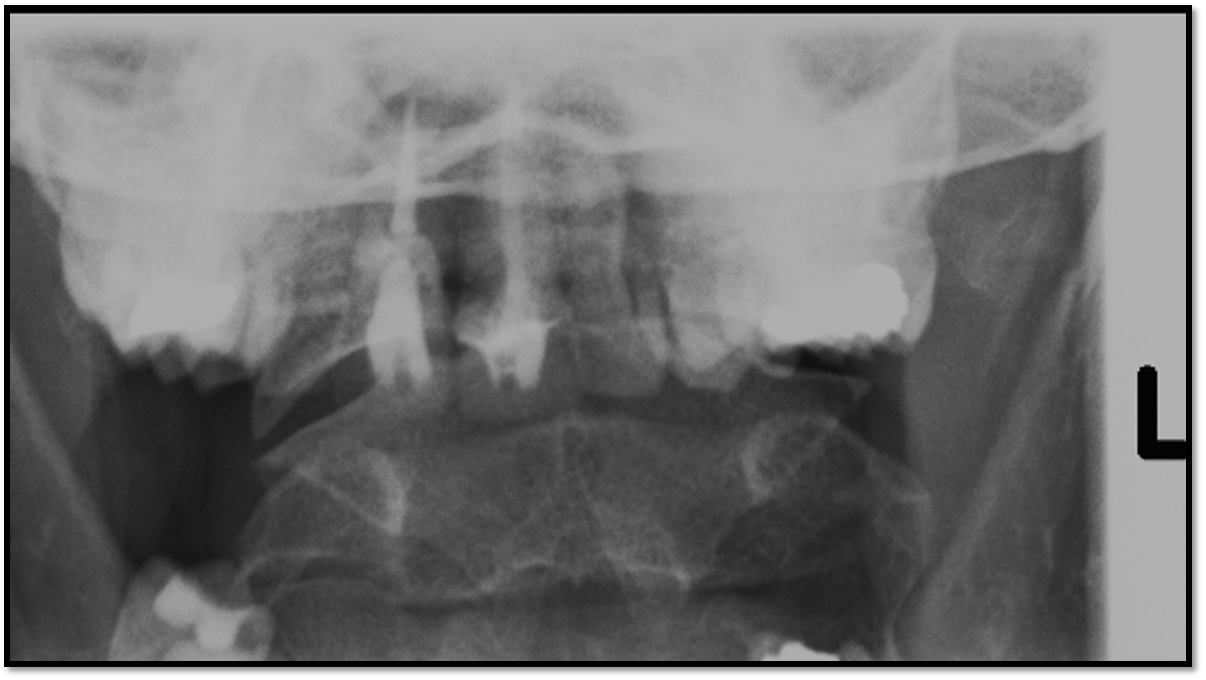

12

Q

AP Axial Cspine criteria

A

• occipital bone and mandible lined up (extension)

• spinous process midline (rotation)

• open vertebral discs (angle)

• all of C3 is visible

How well did you know this?

13

• need to lift the chin more

• all of C3 is demonstrated

14

• need to lower chin

• good angle

15

• need to increase the cephalad angle

• will move chin inline with occipital aswll